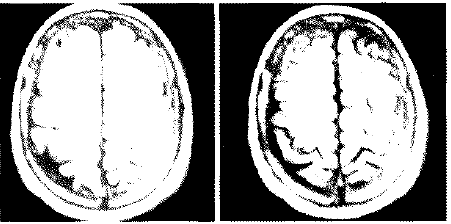

Las imágenes de resonancia magnética muestran un hematoma subdural crónico izquierdo (imagen No. 7). El paciente refiere dormir siempre sobre el lado derecho.

Se aplicó una ampolla intramuscular de Celestote Cronodose® (3 mgrs. de betametasona como fosfato disódico de betametasona y 3 mgrs. de acetato de beta metasona para uso IM., medicamento esteroideo de acción lenta con efecto sistémico máximo de 10 días postaplicación). Y se solicita al paciente dormir del lado del hematoma, del lado izquierdo.

Los controles neurológicos periódicos no muestran signos clínicos de deterioro neurológico, desaparecen totalmente las crisis de paresias en el miembro superior derecho. Las imágenes de resonancia magnética realizada al mes, muestra

Imagen No. 7. Resonancia magnética cerebral inicial.

Imagen No. 8. Resonancia magnética cerebral a las 4 semanas.

Imagen No. 9. Resonancia magnética cerebral a los 3 meses. Se modificaron las imágenes para eliminar los nombres y los datos del paciente.